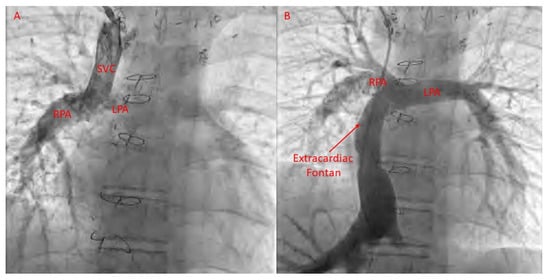

22. Fontan Pathway Obstruction

- Mets, J.M.; Bergersen, L.; Mayer, J.E.; Marshall, A.C.; McElhinney, D.B. Outcomes of stent implantation for obstruction of intracardiac lateral tunnel Fontan pathways. Circ. Cardiovasc. Interv. 2013, 6, 92–100. [Google Scholar] [CrossRef]

- Agasthi, P.; Jain, C.C.; Egbe, A.C.; Hagler, D.J.; Cabalka, A.K.; Taggart, N.W.; Anderson, J.H.; Cetta, F.; Connolly, H.M.; Burchill, L.J.; et al. Clinical Outcomes of Percutaneous Fontan Stenting in Adults. Can. J. Cardiol. 2023, 39, 1358–1365. [Google Scholar] [CrossRef]